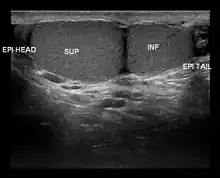

| Ultrasound scan showing a side view of Type A3 polyorchidism, with annotations showing the superior and inferior testes and the head and tail of the epididymis |

- Type A3: The supernumerary testicle shares the epididymis and the vas deferens of the other testicles.

Type A3 is the most common form of polyorchidism, and types A2 and A3 together account for more than 90% of cases.[3] In 65% of cases, the supernumerary testicle is found in the left scrotal sac.[1]